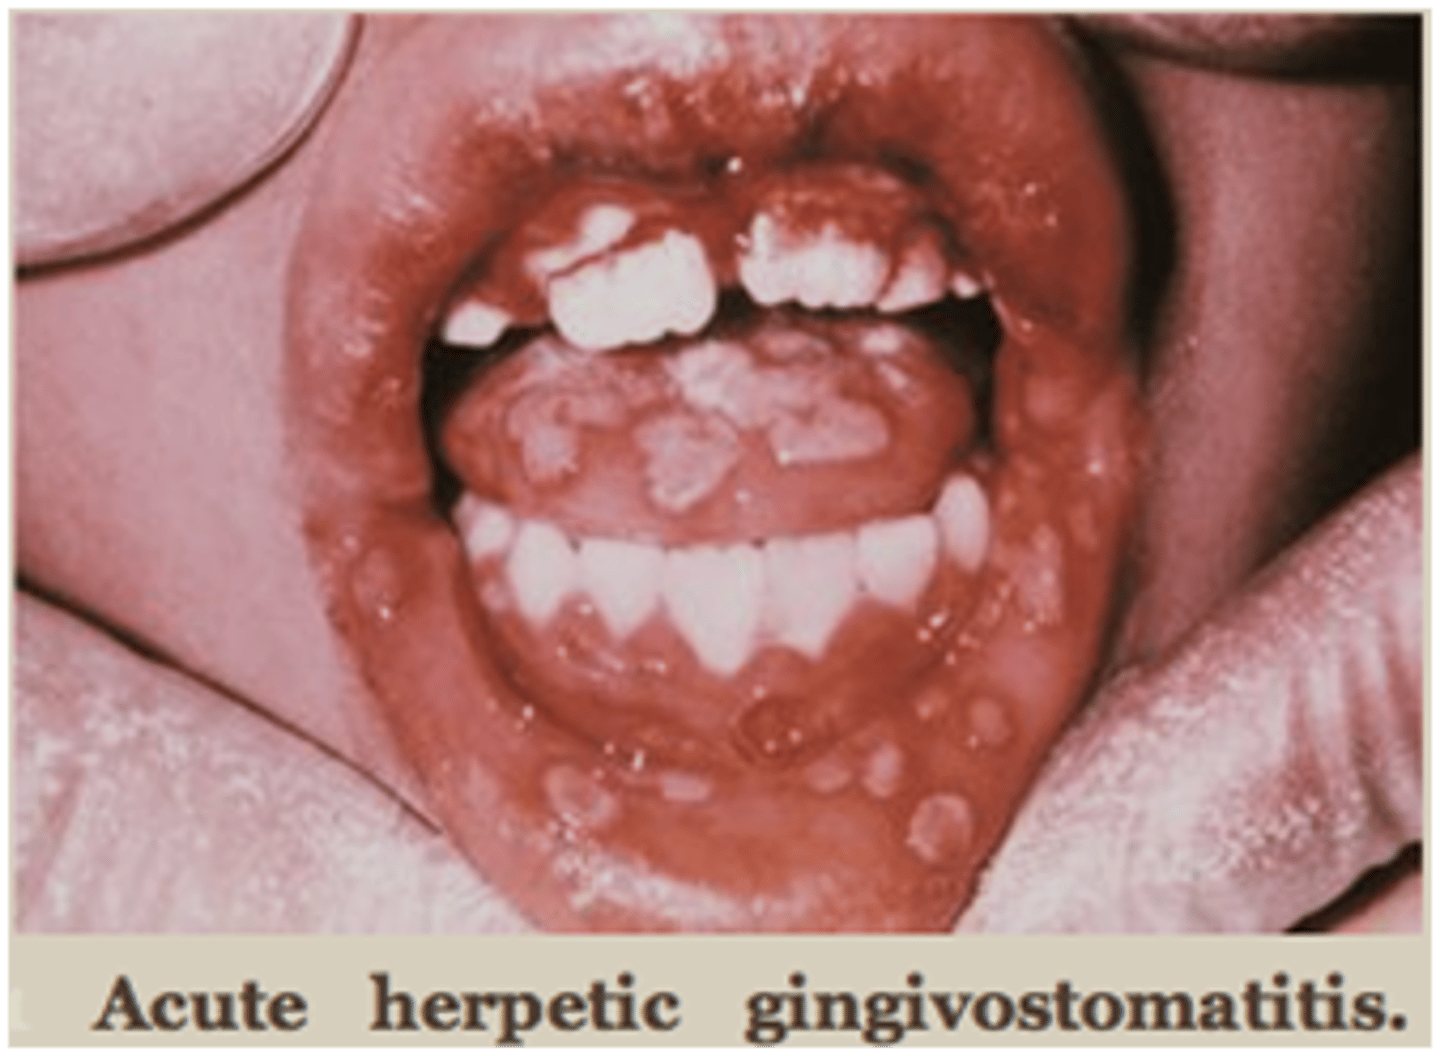

Tzanck test is to diagnose ________ (small painful ulcers that recure every 5-6 months with fever) Treatment is ___ with ____ and analgesics

acute herpactic gingivostomatitis

pallative care with lidocaine rinses and analgesics

Name the pathology: viral infection causing oral ulcers and inflammtion. Mainly affects the children

TX: (3)

herpetic stomatitis

tx: acyclovir, liquid diet and numbing medication , lidocaine rinse if pain severe